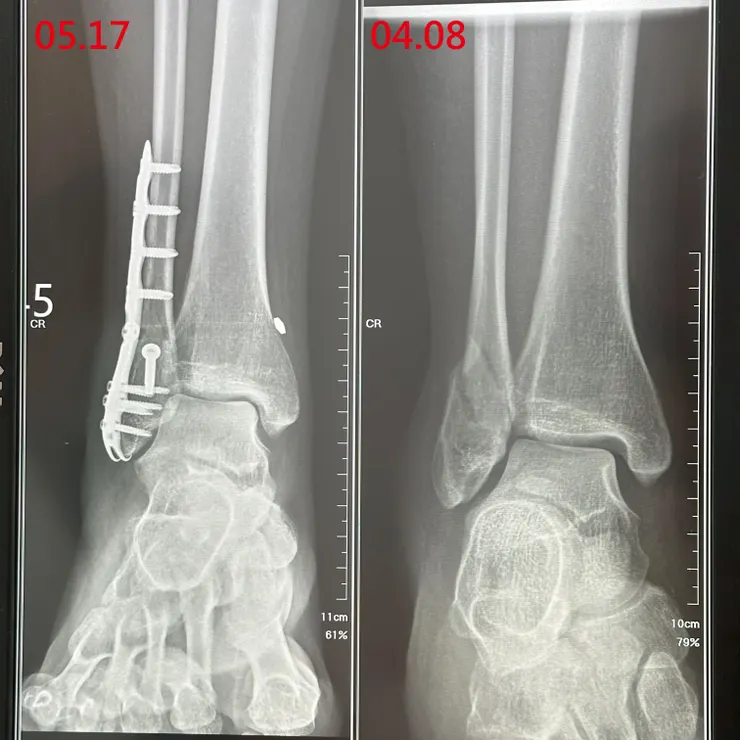

5/17 術後第二次回診

醫生看X光確認骨肉長得很漂亮恢復狀況良好,可以用助行器輔助練習輕輕用腳尖踏著走路,聽到可以練習走路心裡想著從手術後每天乖乖做簡單維持肌力的運動和補充幫助骨肉長好的保養品的努力都值得了,光這樣腳尖走路就對全身的施力減緩很多,離開前還跟醫生許了個想要光速復原恢復正常生活,許了個端午節能不靠助行器就能慢慢走路的願望,醫生說了要看下個月的恢復狀況才能看這個小願望能不能實現了